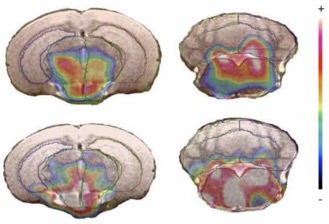

β SB-258585 reduces food motivation while blocking 5-HT6 receptors in the non-human primate striatum

M. Pitoy, L. Gauthier, J. Debatisse, J. Maulavé, E. Météreau, M. Beaudoin, K. Portier, V. Sgambato, T. Billard, L. Zimmer, S. Lancelot, L. Tremblay

Prog. Neuro-Psychopharmacol. Biol. Psychiatry 2024, 131, 110970